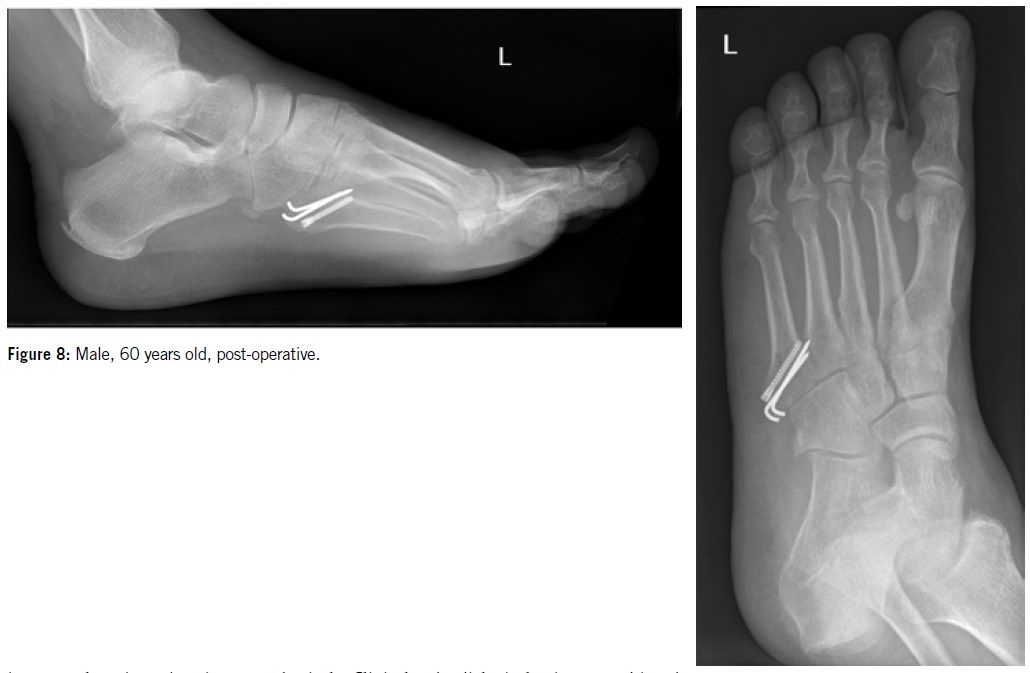

In 1975, Dameron2 was the first to suggest that athletes should undergo early operative treatment to prevent delayed union. Various surgical techniques have since been proposed, including intramedullary screw fixation, plating, percutaneous pinning, intramedullary curettage, and bone grafting (Figures 7 & 8). While the reported union rates with these methods are generally high, several complications have also been documented following their use.

Over the past 25 years, intramedullary screw fixation has emerged as the most widely used surgical technique for treating proximal fifth metatarsal diaphyseal fractures in athletes, with reports indicating improved union rates and faster recovery times. The partially threaded cannulated screw became the gold standard for operative treatment.

More recently, excellent bone healing outcomes have been reported with the use of headless compression screws. It is recommended to use the largest diameter screw that fits the width of the intramedullary canal, with a minimum diameter of 4 mm and a length of at least 50 mm. Proximally, the screw should be positioned to avoid irritation of the cuboid or the fourth/fifth intermetatarsal joint.

Due to the dorsal curvature of the proximal fifth metatarsal, proper care must be taken to ensure that the screw tip aligns as closely as possible with the bone’s axis. However, recent studies have reported several cases of failure following screw fixation in athletes9. The most frequently cited cause of delayed union and refracture is an early return to vigorous physical activity.